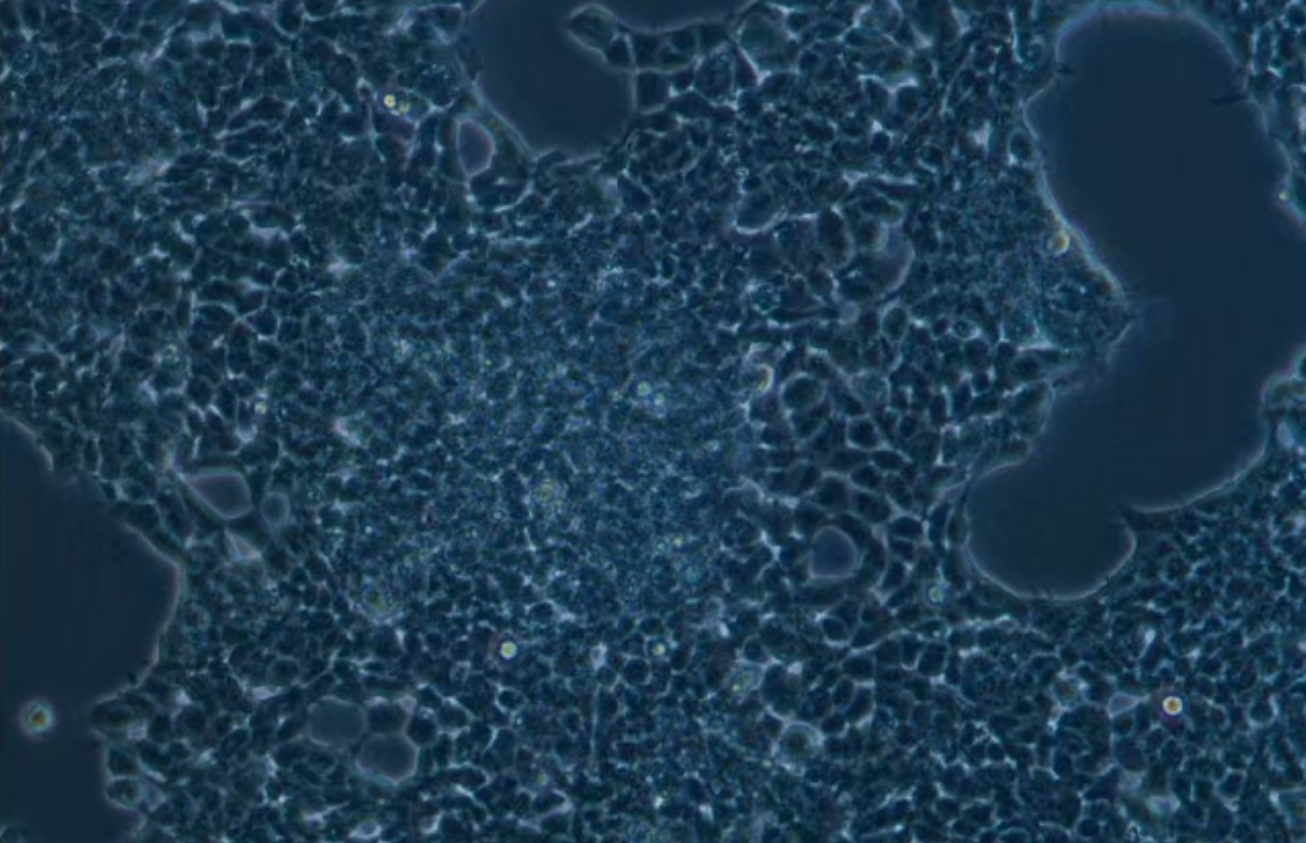

形態 |

上皮細胞樣 |

生長特征 |

貼壁,懸浮混合生長 |